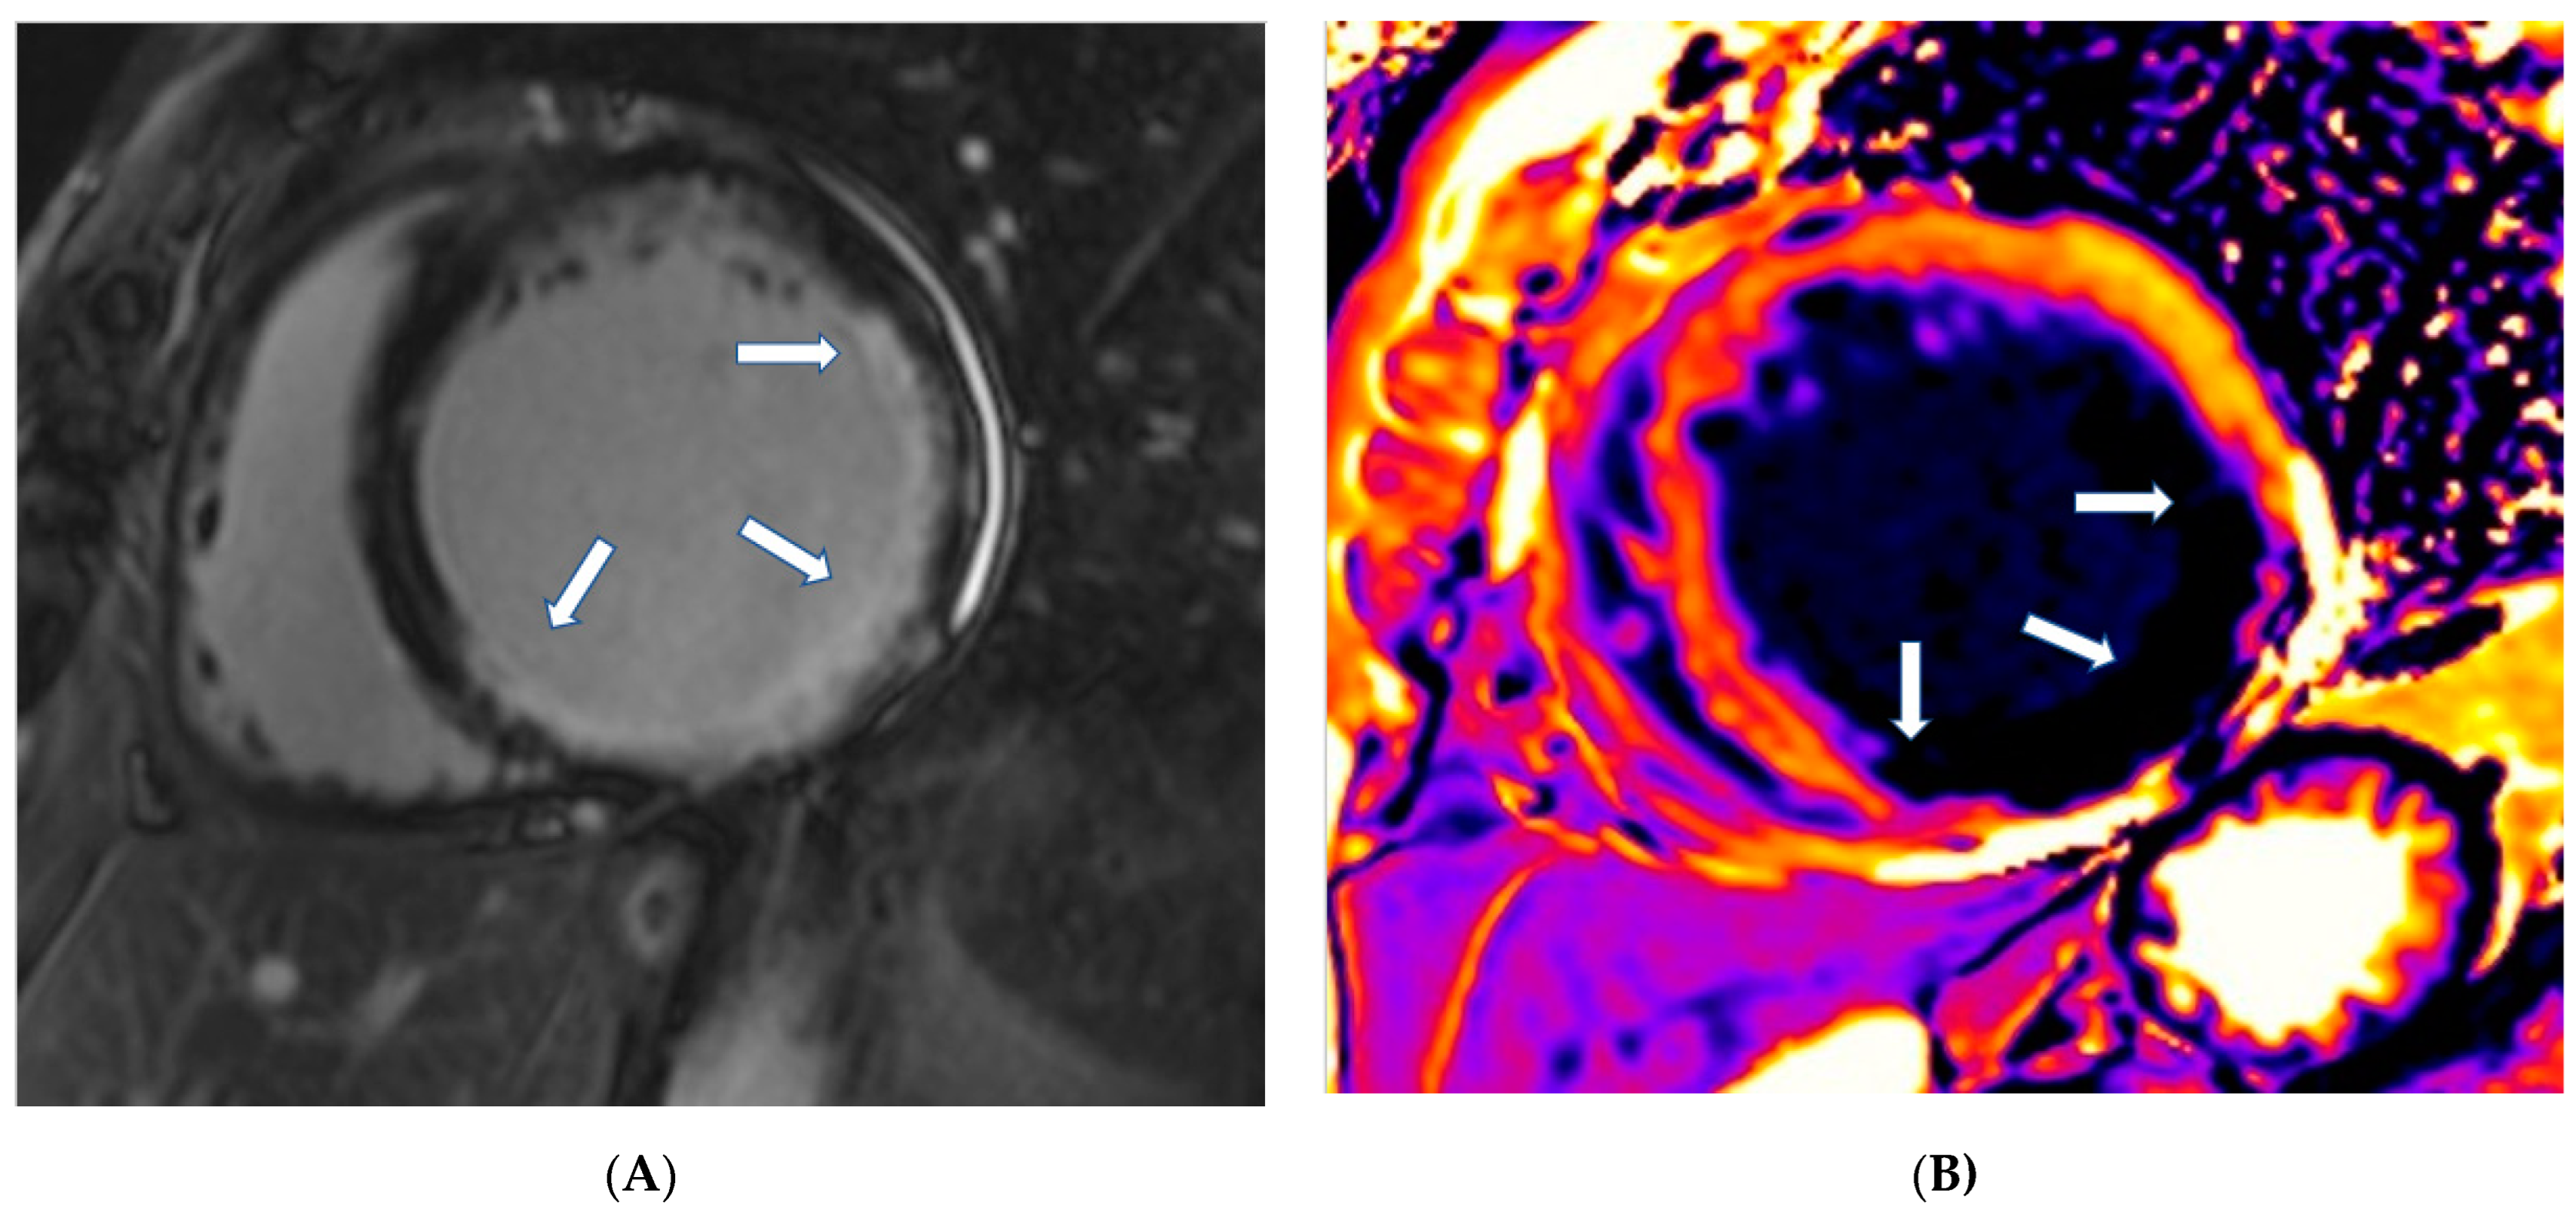

- T1-weighted images (T1-W) and late gadolinium enhancement (LGE): T1-W imaging provides information for a morphological assessment of the heart. Late gadolinium-enhanced T1-W images (LGE), taken 10–15 min after gadolinium-based contrast administrations using inversion recovery pulse sequences, allows for the detection of myocardial replacement fibrosis (scar) (Figure 1) [13]. LGE may also detect marked extracellular interstitial expansion in association with amyloidosis (amyloid deposition and fibrosis) and in pulmonary hypertension (myocardial disarray with increased collagen content without focal replacement fibrosis). In myocarditis, LGE mainly reflects inflammation, combined with or without fibrosis [13]. In the acute phase of myocarditis, LGE correlates with necrosis (associated with edema as assessed by T2 mapping), while in the chronic phase, it corresponds to fibrosis (with less or no edema) [13]. Thrombi (if not organized) do not accumulate contrast agents, making LGE ideal in excluding recent thrombi [14].

Figure 1. (A) Short-axis LGE image showing myocardial infarction (arrows) in the inferolateral wall of LV. (B) Matching native T1 mapping of the same patient.Myocardial infarction is characterized by subendocardial or transmural LGE in the distribution of epicardial coronary arteries. Subepicardial or patchy LGE usually in the inferolateral wall is characteristic of myocarditis. Finally, diffuse subendocardial LGE that does not follow the typical distribution of epicardial coronary arteries is often associated with microvascular coronary artery disease, vasculitis, antiphospholipid syndrome, and endocrine disorders, such as Cushing syndrome and autoimmune thyroid disease [13]. - (b)